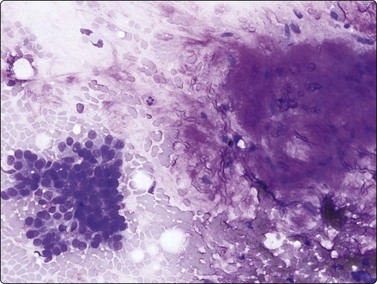

image

Fig. 8.1 Bronchiolar epithelium

Small sheet of regular glandular cells (Pap, HP).

Bronchial epithelium may be abundant in percutaneous FNB if the needle traverses a medium-sized bronchus or tracks along a bronchial lumen. Transbronchial FNB may also yield abundant bronchial epithelium. Bronchial epithelium appears as small palisaded clusters with a ciliated border. In large aggregates the cells may present as flat sheets with a pavement-like aspect, but ciliated cells can usually be observed at the edges of these sheets.

Bronchiolar epithelium or nonciliated epithelium is seen commonly as sheets of various size (Fig. 8.1). They usually have irregular edges and the component cells display variable cell separation. The nuclei are generally small and there is a low nuclear:cytoplasmic (N:C) ratio. Sometimes the nuclear outlines are slightly irregular and small intranuclear cytoplasmic inclusions are observed. Occasionally, atypia of bronchiolar epithelium may be quite pronounced, for example in reactive or inflammatory processes; however, the number of atypical cells is usually small. A diagnosis of malignancy should generally not be made on the basis of small numbers of cells.